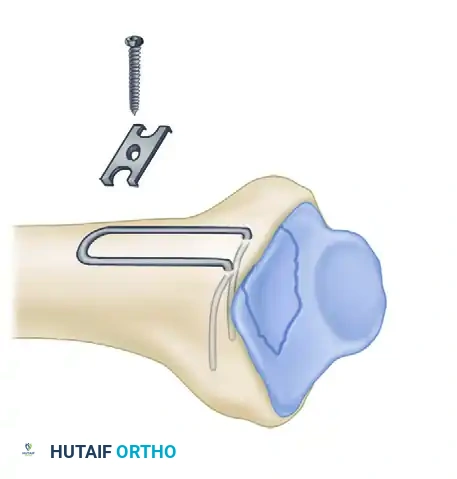

Biomechanics of Pin-Plate Fixation

Traditional radial styloid Kirschner wire fixation provides only a single point of constraint. This single point of fixation acts as a pivot, failing to prevent settling, bending, or radial drift of the distal fragments under physiological loads.

By adding a small buttress plate to the radial styloid pin, the construct is transformed. The pin-plate provides two distinct fixation points: the first through the distal end of the plate, and the second through the intact medial radial cortex. This dual-point constraint prevents collapse, resists dorsal torque, and halts radial migration.

Fragment-Specific Implants and Application

1. The Radial Pin-Plate:

2. The Ulnar Pin-Plate:

The dorsal ulnar fragment (often involving the sigmoid notch) is stabilized with an ulnar pin-plate. By proper contouring, this plate can close gaps in the sagittal plane,